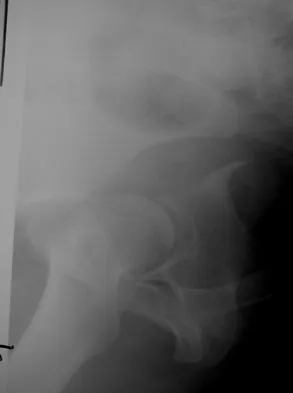

Figures 22a and 22b show the radiographs of a patient who reports stiffness of the hip and associated pain. Management should consist of

The patient has grade IV heterotopic ossification with the limb in an abnormal nonfunctional position. Treatment should consist of excision of the bone to restore hip motion and prophylaxis to prevent recurrent formation. The best time to excise the bone is controversial, with no conclusive evidence supporting early or late excision. Pellegrini VD Jr, Koniski AA, Gastel JA, Rubin P, Evarts CM: Prevention of heterotopic ossification with irradiation after total hip arthroplasty: Radiation therapy with a single dose of eight hundred centigray administered to a limited field. J Bone Joint Surg Am 1992;74:186-200.

- Warren SB, Brooker AF Jr: Excision of heterotopic bone followed by irradiation after total hip arthroplasty. J Bone Joint Surg Am 1992;74:201-210.